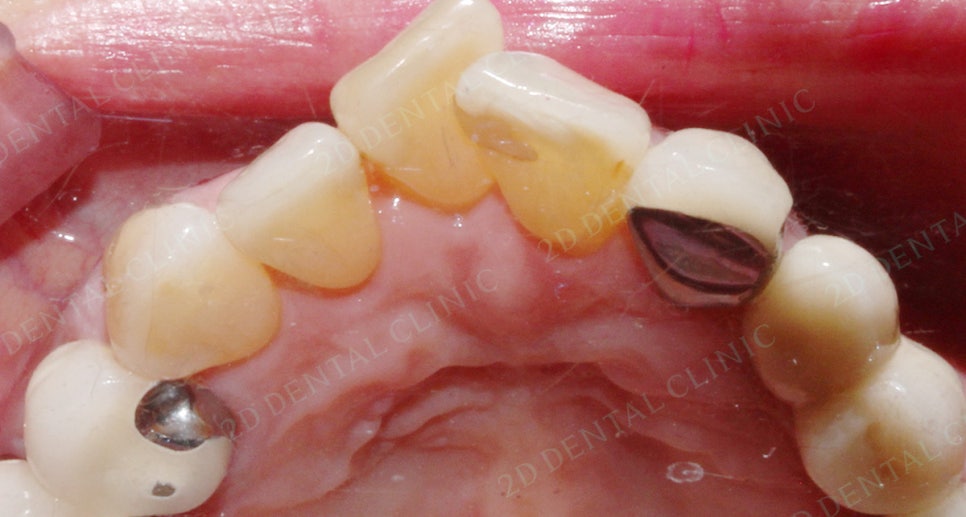

앞니교정 잇몸질환 예방 투디교정 (전)

<치료 전 상태>

실제로 40대 이상 환잔분들은

앞니가 삐뚤거리는 부위에 치석이 심하게 침착되있어요.

앞니 부분과 하악 앞니 앞쪽이 심하기 때문에

치석제거가 1차 진행

그리고 잇몸질환이 어느 정도 진행된 상태며

치아 사이의 공간(블랙 트라이앵글) 이 존재해요.

또한 앞니 삐뚤어짐으로 인해

다물어진 입술이 살짝 불편해 보여요.